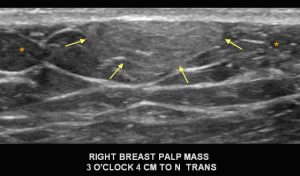

With the mammogram appearing negative, a diagnostic ultrasound was performed. What is the diagnosis?

Explanation: This is a circumscribed, oval, hyperechoic mass, which is consistent with a lipoma. They have the same imaging appearance in males and females. They may appear as circumscribed fat-containing masses on the mammogram, particularly if the patient has a lot of fibroglandular tissue. Since this male’s breast is composed predominantly of fat density, the lipoma cannot be easily discerned on the mammogram. On ultrasound, a lipoma (arrows) is either isoechoic or slightly hyperechoic to the surrounding subcutaneous fat (*). Lipomas are benign and when correctly identified on imaging, they do not require further follow-up.